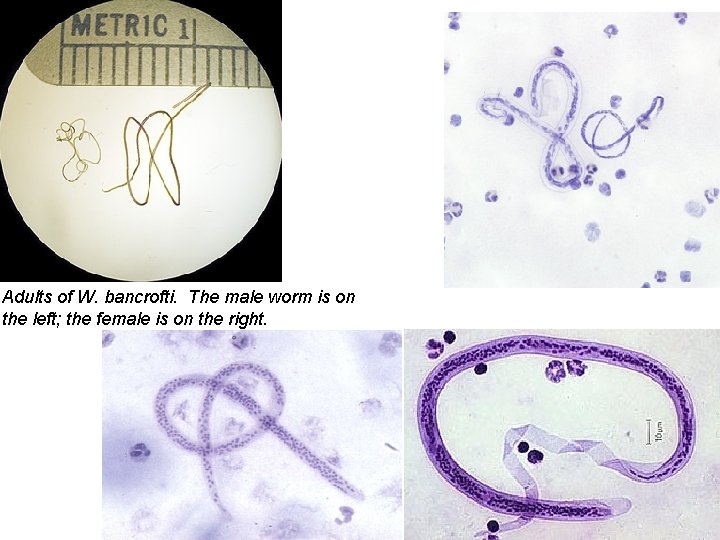

Adults of W. bancrofti. The male worm is on the left; the female is on the right.